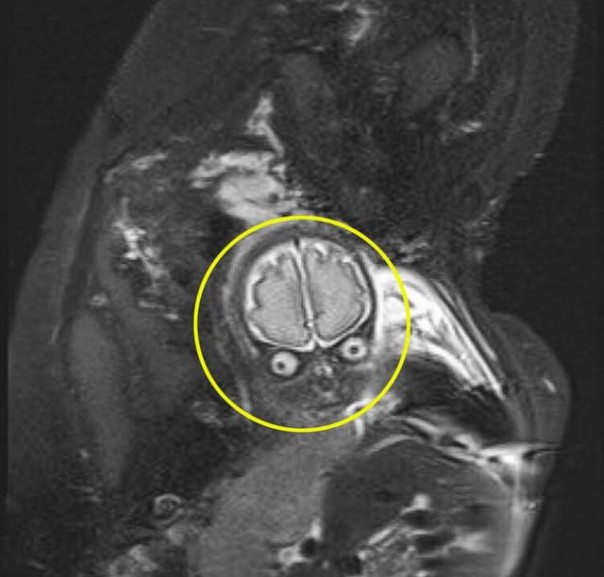

Лаура Томас, которая находилась на 30-й неделе беременности, и её партнёр Мэтью Тэнсли были в шоке, когда увидели на МРТ своего будущего ребёнка. На снимке их нерождённый сын был похож на марсианина из фильма "Марс атакует!" Тима Бёртона, сообщает The Sun.

Впрочем, это нисколько не напугало будущих родителей, а лишь рассмешило, ведь малыш оказался совершенно здоровым. Дело в том, что врачи заподозрили, что у мальчика может быть избыток жидкости в мозге, но сканирование показало, что всё в порядке.

"Врач предупредила меня, что изображения будут сильно отличаться от стандартного 2D-сканирования, но я не ожидала, что он будет выглядеть вот так. Сначала я, конечно, испугалась, но в итоге вышло очень смешно" - Лаура Томас. Источник